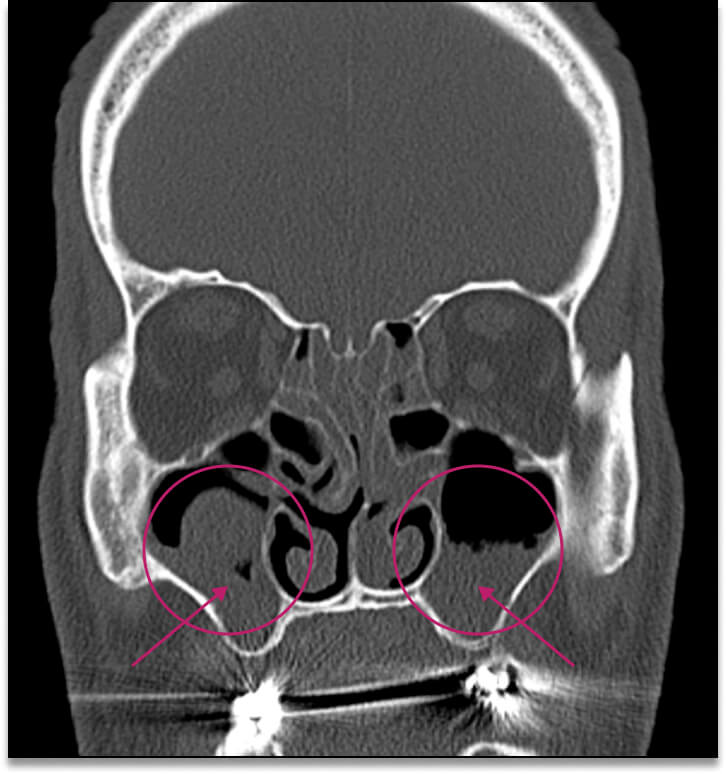

Сүүлийн жилүүдэд мэргэжилтнүүд харшлын ринит ба олон төрлийн хамар, хамрын дайвар хөндийн үрэвсэл хоорондын харилцаа хамаарлын талаар их ярьдаг болж. Энэхүү харилцаа холбооны механизм гүйцэд сайн судлагдаагүй байгаа ч харшлын риниттэй өвчтөнүүдэд архаг хамар, хамрын дайвар хөндийн үрэвсэл үүсэх магадлал өндөр гэж үздэг.

Компьютер томографын доорх зурагт хамрын дайвар хөндийн (хөндлөн зүсэлт)-ийг харж болно. Эрүүл хүнд (зүүн талынх) дээд эрүүний хонх нь цэвэр, өргөсөөгүй, салс зузаараагүй, хонх хэсэгт саарал сүүдэр ажиглагдаагүй байна. хамар, хамрын дайвар хөндийн үрэвслийн үед (баруун талын зураг) КТ-т эрүүний хонхнуудын доод хэсгүүдэд ихэнхдээ тэгш бус ирмэгтэй нягт сүүдэр тодорхойлогдож байна. Хамрын суваг салс хавагнасан байна.